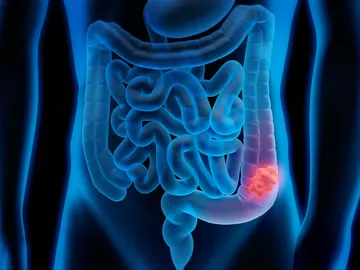

Este medicamento común podría evitar la recaída en el cáncer colorrectal

Asocian el parásito Anisakis con cáncer de colon